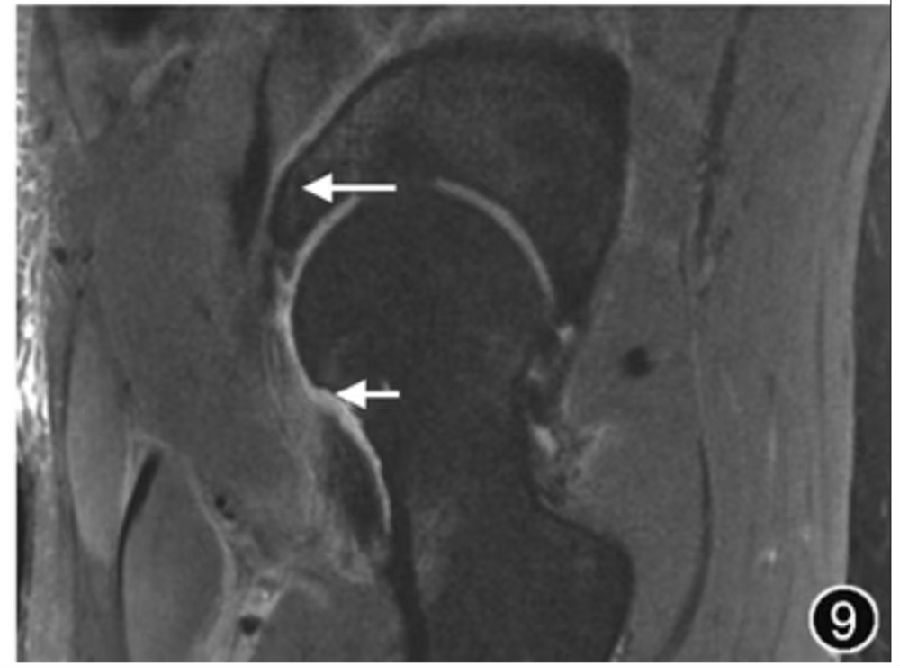

8.髋关节术后评估:髋关节镜检查、盂唇手术、骨软骨成形术(图9)及髋关节置换术等在髋关节损伤患者中应用广泛。在盂唇修复术后,若观察到明显的液性信号进入盂唇和/或盂唇软骨交界处时,可诊断残留撕裂或复发性盂唇撕裂。髋关节置换术后复查时,MRI是评估假体周围骨溶解和滑膜炎最准确的影像学检查方法,还可以评估术区相关肌腱和神经血管结构。髋关节置换术后影像学评估应考虑到常见的术后并发症,主要包括假体周围骨溶解、假体松动移位、术后感染、关节积血、滑膜炎、隐匿性不全骨折、异位骨化及周围肌肉肌腱变性和撕裂等。其他髋关节手术方式,如股骨颈骨折内固定,应注意明确是否合并股骨头缺血性坏死等术后并发症。

图9 髋关节撞击术后MRI图像。冠状面T2WI示髋臼钉道(长↑)及股骨头颈局部骨质缺损(短↑),周围软组织水肿